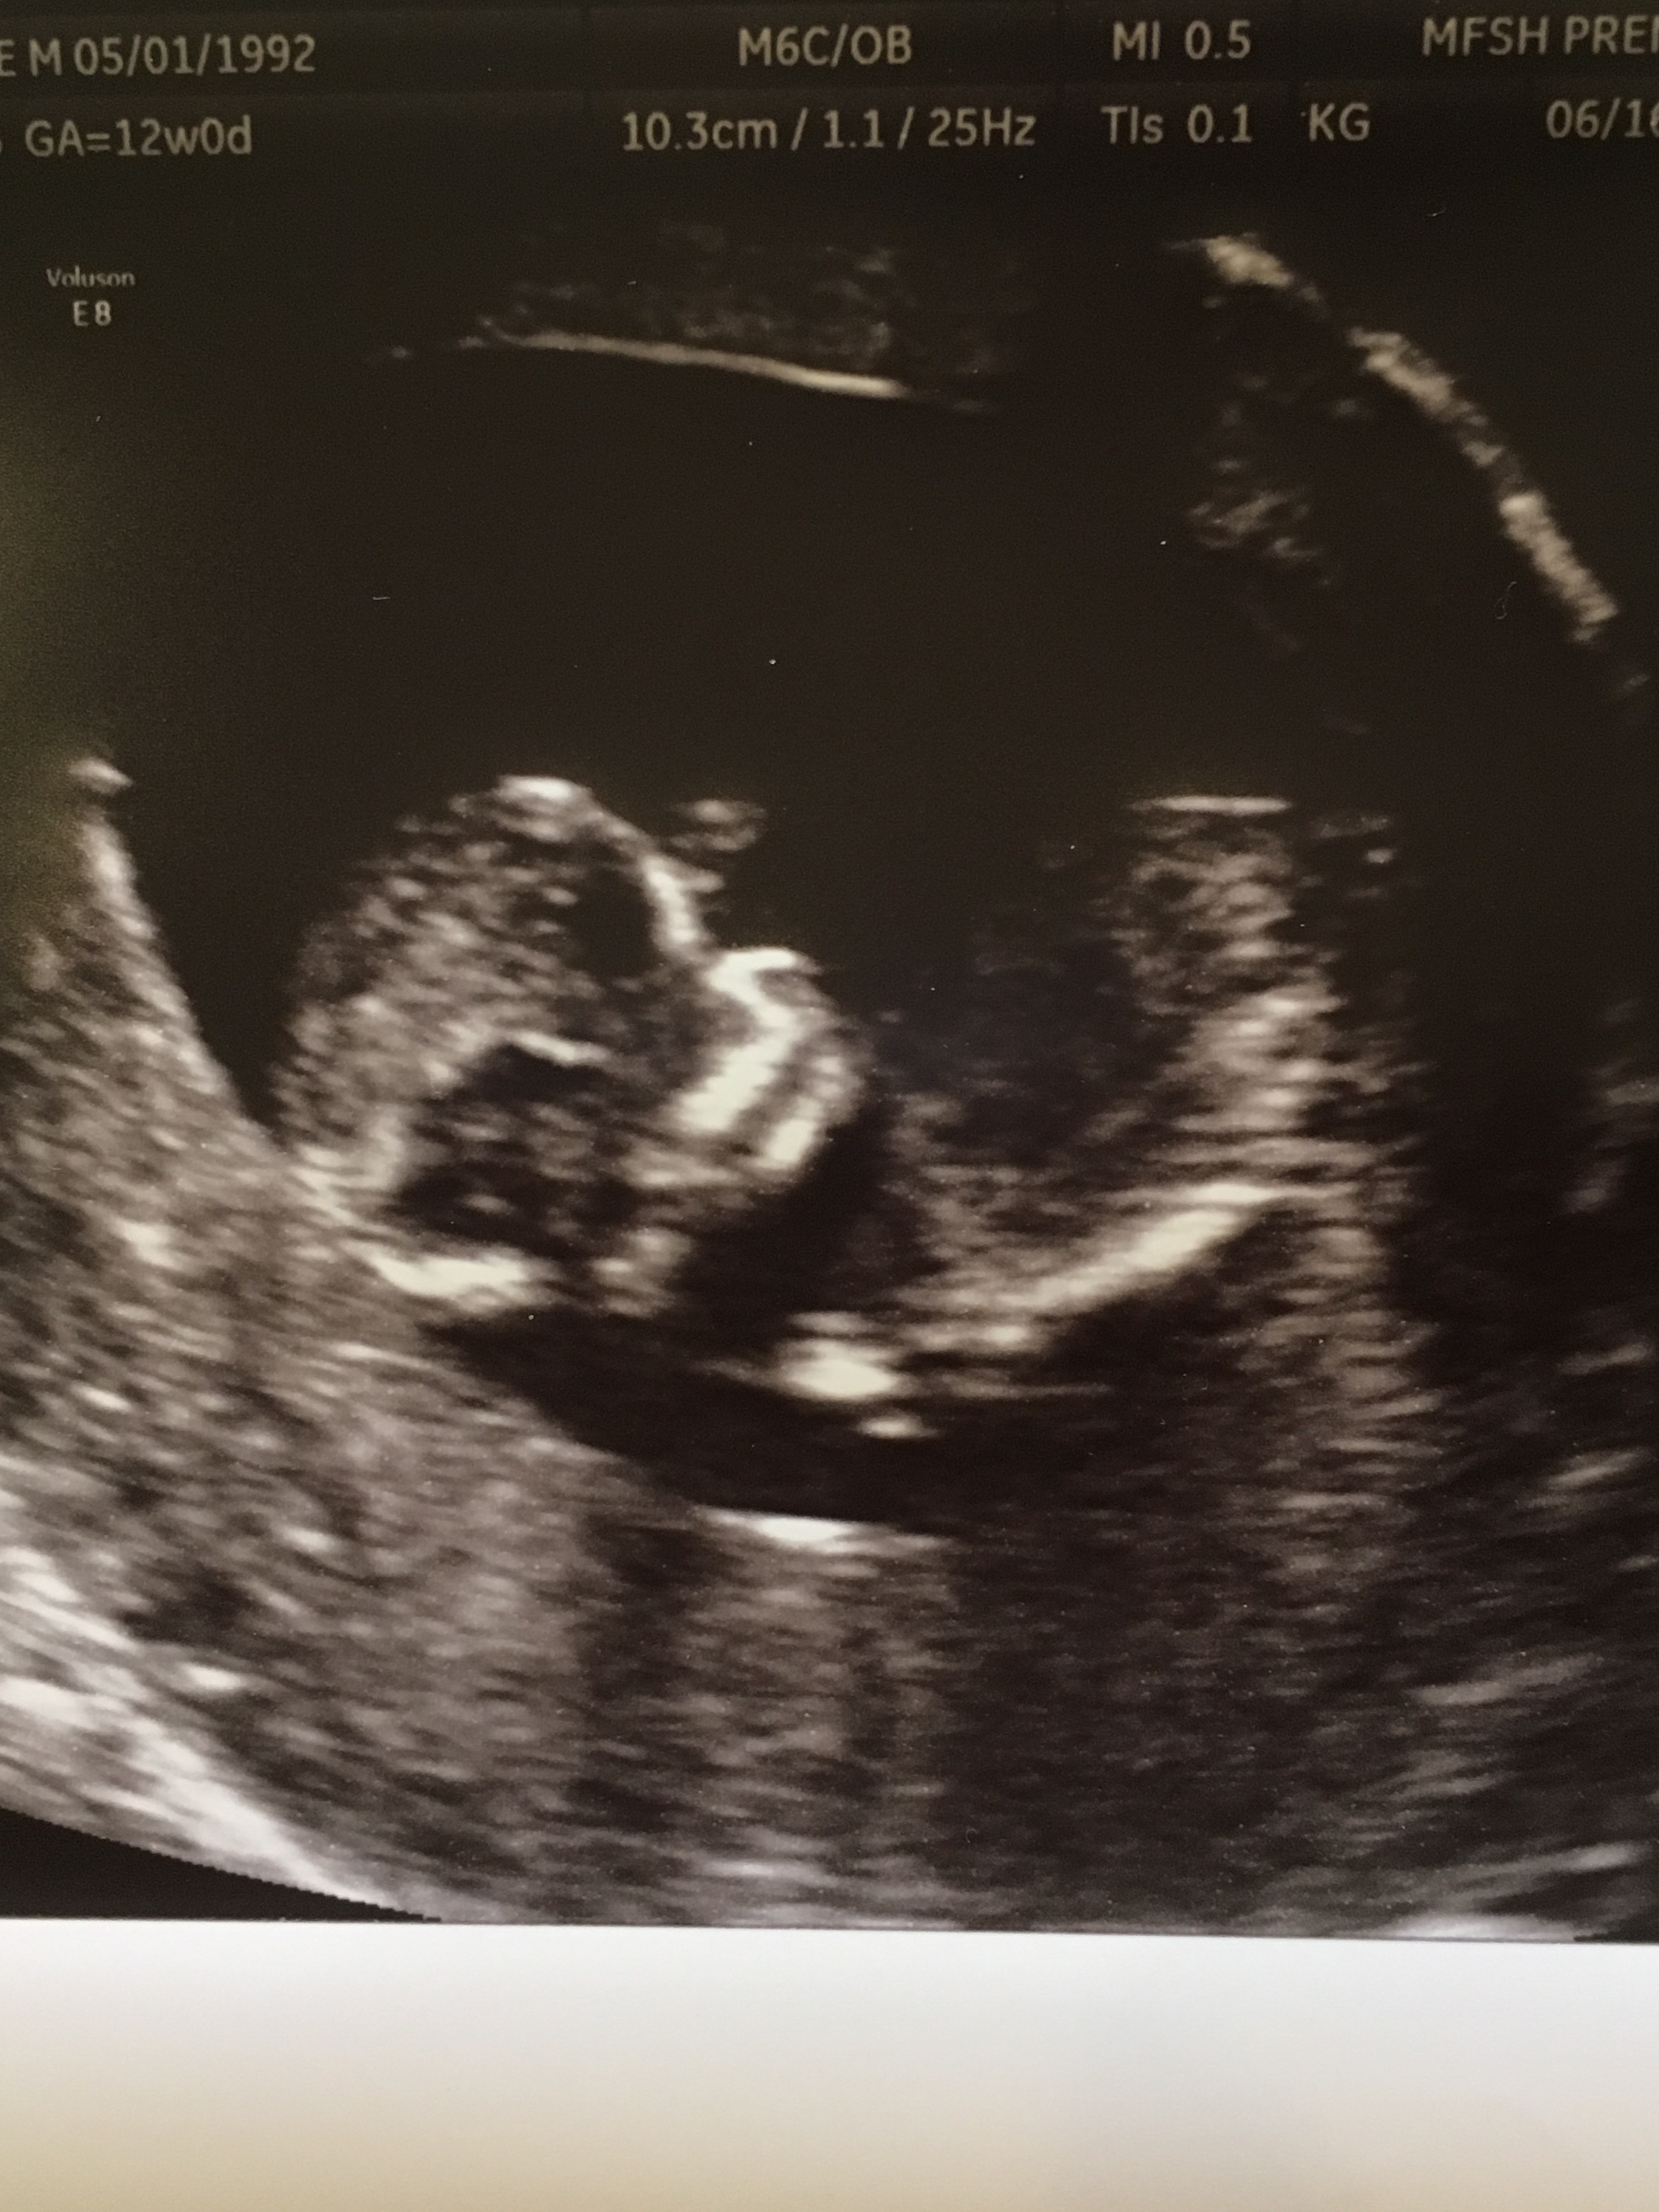

Any guesses based on skull/nub theory? Thanks in advance!!!Attachment 36635Attachment 36636